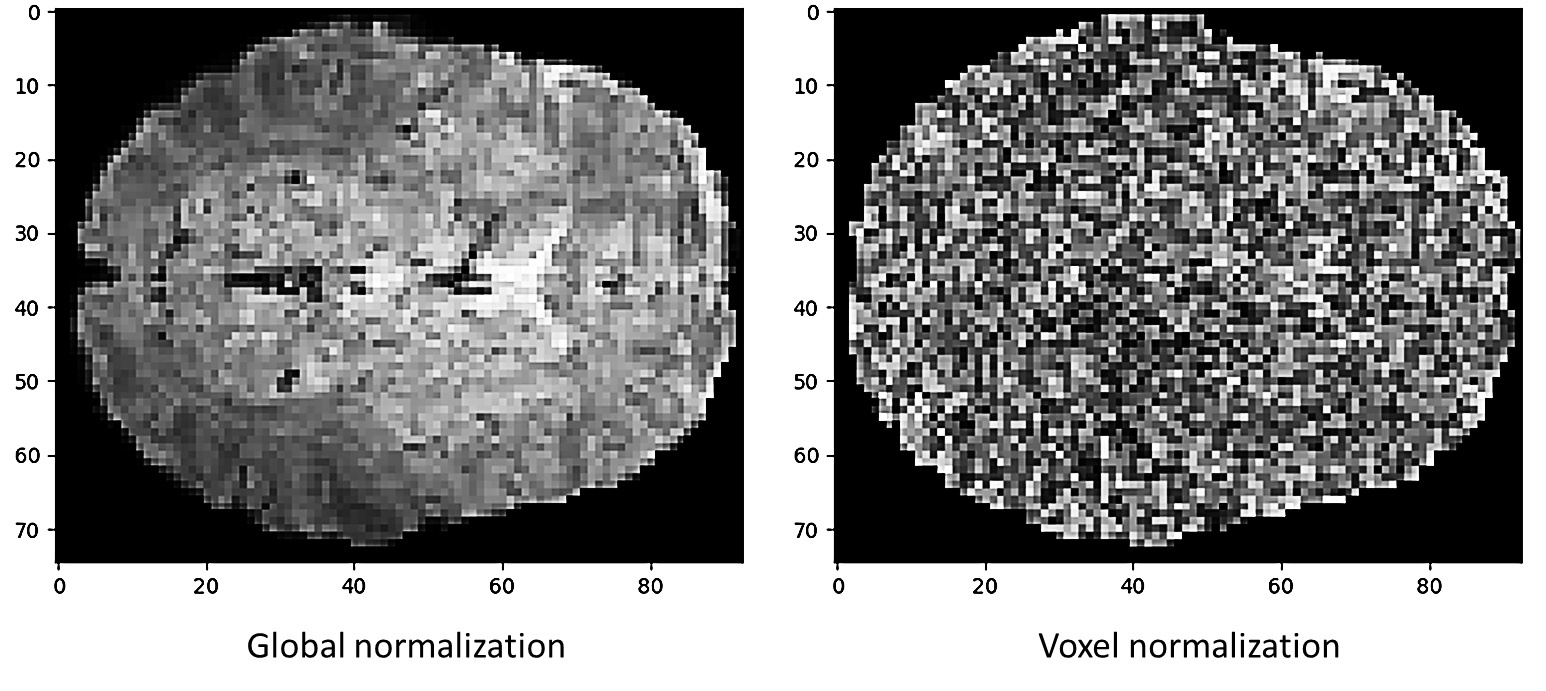

Given an fMRI scan, with frames, , where each is a volumetric data point representing the acquired pulses and echoes in a given interval, where are the width, height, and depth of the acquired data. We first map each frame into two representations by applying two normalization techniques. The first technique applies global normalization, utilizing standard z-score normalization over the entire scan. The second applies voxel normalization, which separately z-score normalizes the values of each voxel over the time domain.

The global normalization, denoted by , can be expressed as where are the mean and standard deviation of the entire 4D volume . By focusing on the dimension of a specific frame, the voxel normalization, denoted by , can be expressed as where are the mean and standard deviation of the voxel , across all frames in .

Voxel normalization emphasizes the relative activation of a specific voxel in a given interval, while suppressing structural information, see Fig. 4 in the supplementary materials. We denote the concatenation on the channel dimension of the two normalized representations of the entire scan as .

The voxel normalization emphasizes the temporal activations of specific voxels in a given sequence and suppresses the structural information in the acquired scan. A representative sample of the voxel normalization along with the global normalization of the same slice can be seen in Fig. 2